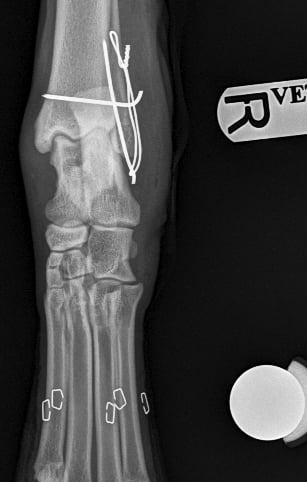

Orthogonal xrays reveal a lateral malleolus fracture (Fig.1 and 2), stress views and palpation revealed stable joint with no affection of collateral ligaments but due to the fracture there is some degree of rotational instability. Surgical stabilization is strongly advised as Buddy is a 40 kg patient.

Lateral approach to the talocrural joint reveals severe oedema and bruising, 1.2mm IM pin placed in a distal to proximal fashion, 0.75mm cerclage wire used to create a figure-of-8 tension band. 1.4mm pin placed parallel to the talocrural joint from lateral to medial (Fig 3 and 4).

Fig. 1